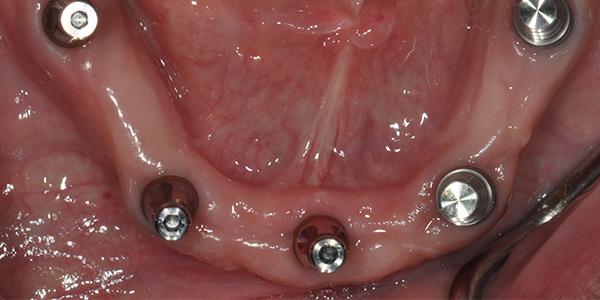

During Mandibular Arch